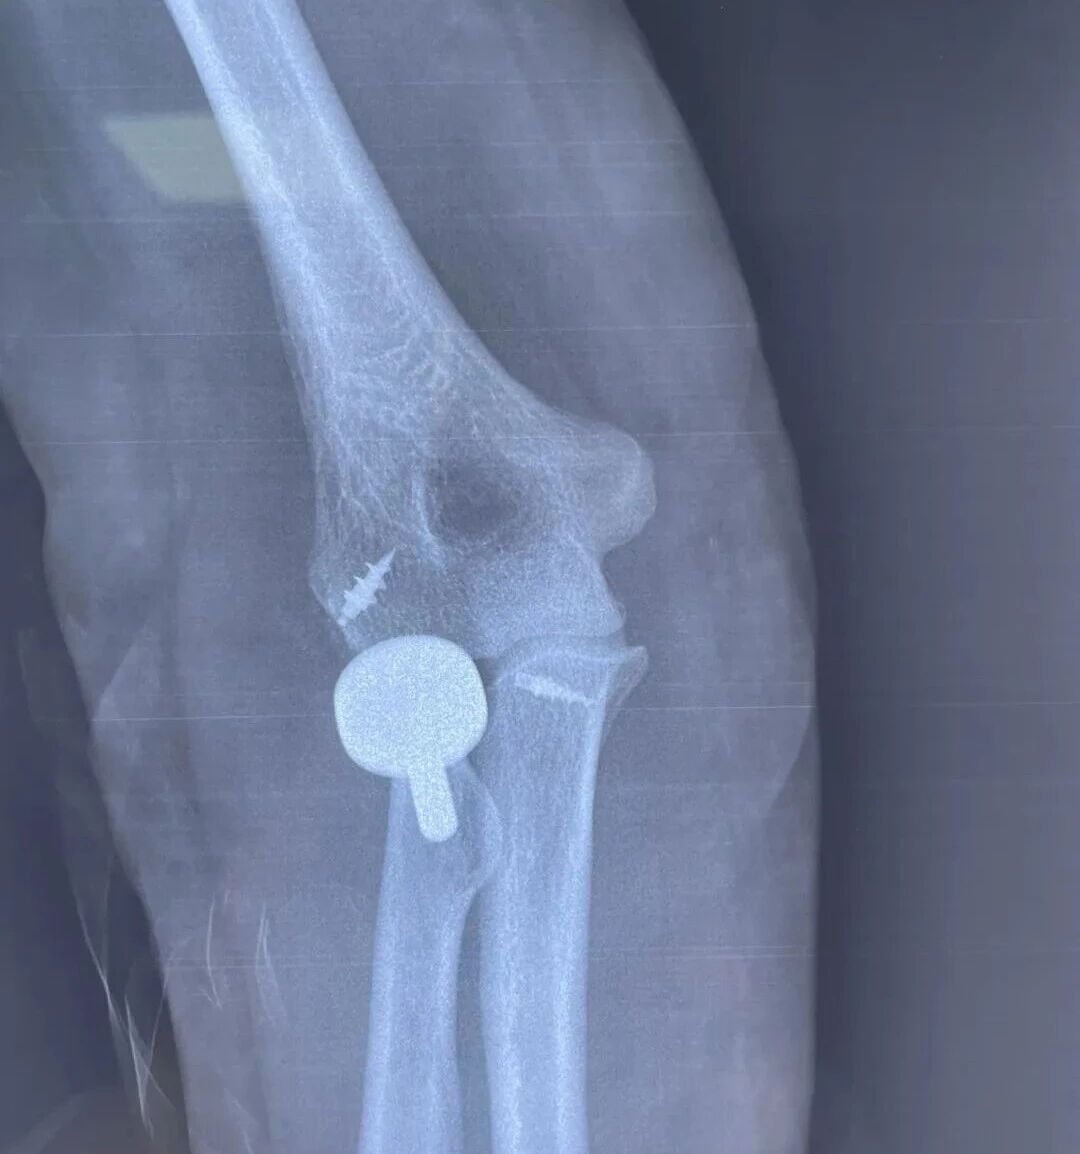

趙女士術(shù)后復(fù)查X片顯示,人工橈骨頭固定位置精準(zhǔn)、穩(wěn)固。在醫(yī)護(hù)團(tuán)隊(duì)的指導(dǎo)下,她術(shù)后盡早開展了功能鍛煉,目前肘關(guān)節(jié)伸直、屈曲功能已接近正常水平,恢復(fù)情況十分理想,趙女士對(duì)此非常滿意。